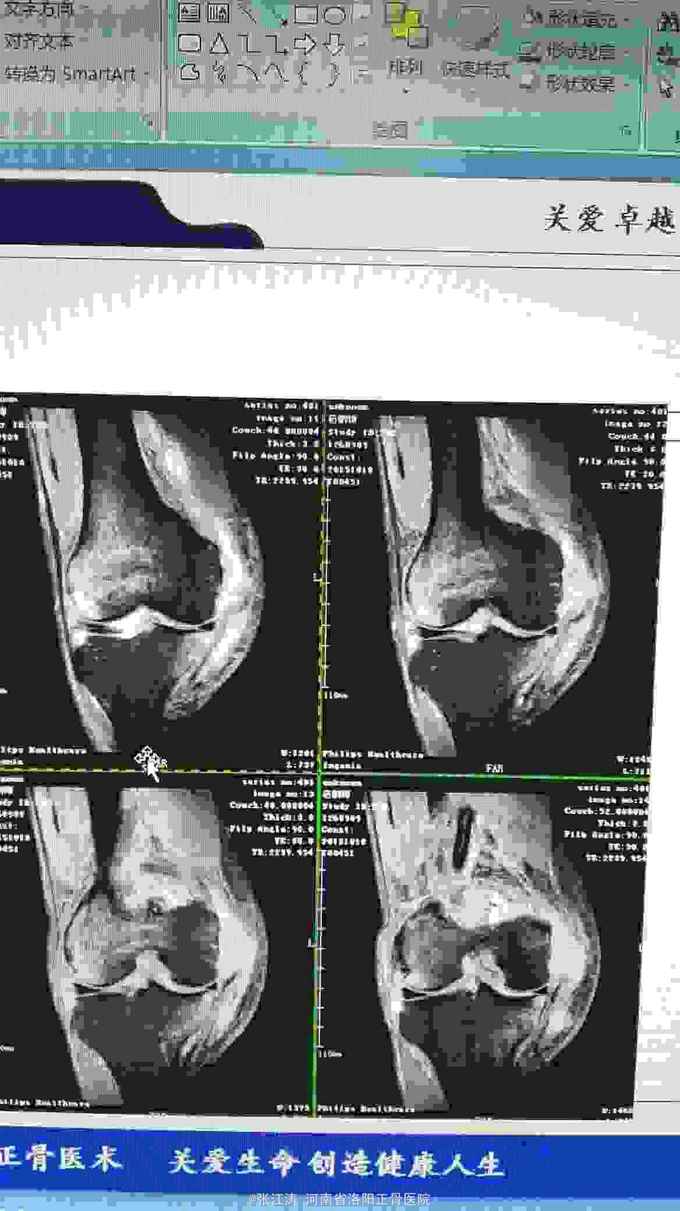

车祸致伤膝关节脱位3天住院,受伤后未做相应处理,仅行MRI检查。

膝关节前后抽屉试验及外翻应力实验阳性,末梢血液循环及感觉运动良好

膝关节脱位,前后交叉韧带损伤及内侧副韧带损伤